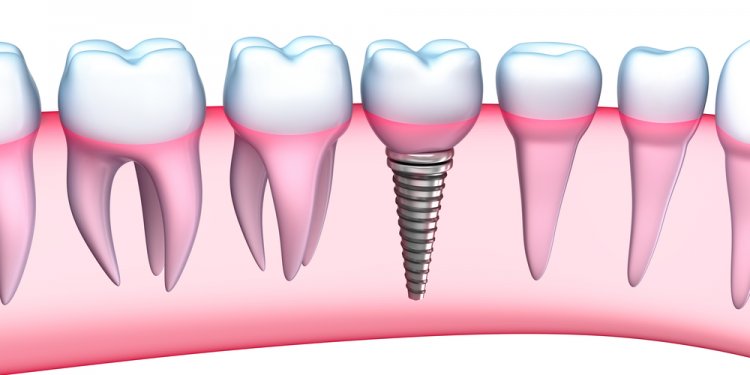

What are dental Implants? A dental implant is an artificial tooth root that is placed into your jaw to hold a replacement tooth, bridge or even a full denture. Dental implants are made of pure titanium, a material that is totally bio compatible (compatible with body tissues) and actually integrates with the surrounding bone and becomes part of the body. Dental implants are…

What are Dental implants?

Dental implants are artificial tooth roots that provide a permanent base for fixed, replacement teeth. Compared to dentures, bridges and crowns, dental implants are a popular and effective long-term solution for people who suffer from missing teeth, failing teeth or chronic dental problems. Because they fit, feel and function like natural teeth, dental implants are quickly…

Once you have strong bone and healthy surrounding gums, you’re ready for the implant surgery. Before the operation, you’ll receive either a local anesthetic or general anesthesia. The oral surgeon begins by making a series of incisions to create a flap of gum to retract. He or she then uses a series of progressively wider drills to open the hole gradually. When the hole in…